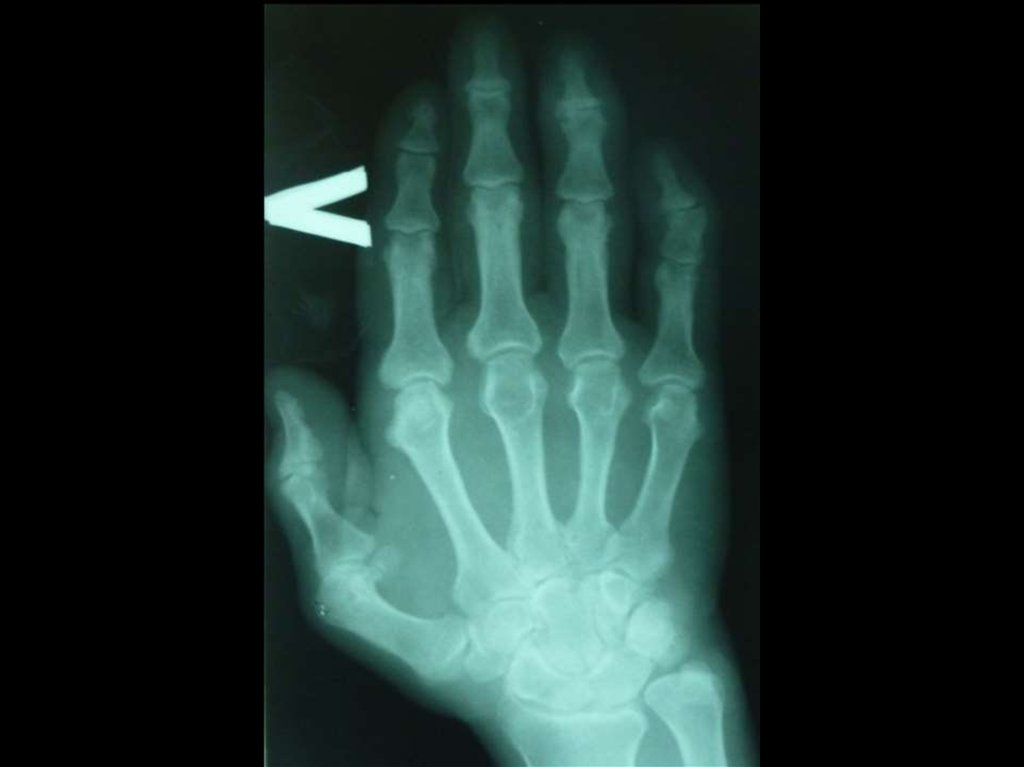

деформация суставов за счёт костных разрастаний,

включая узелки Гебердена;

несимметричное сужение суставной щели (R-признак);

остеосклероз суставной поверхности (R-признак)

остеофитоз.